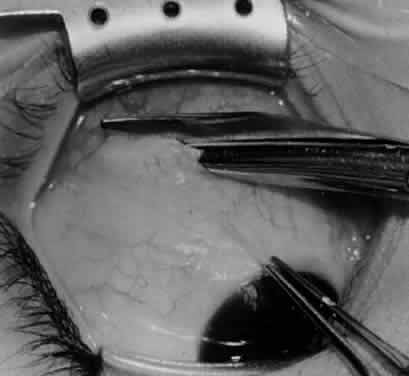

Fig. 3. The eye is retracted superonasally with the 4-0 silk traction suture. The suture is attached to the drapes with a hemostat. A Stevens hook is placed along the inferior border of the lateral rectus muscle and drawn temporally. A von Graefe hook is placed within the incision and drawn inferotemporally to expose the inferior oblique muscle.

Fig. 4. A stiff iris repositor can be placed against the sclera to depress the sclera and enhance the view of the inferior oblique muscle. The inferior temporal vortex vein adjacent to the Stevens hook is retracting tissue along the inferior border of the lateral rectus muscle. The second Stevens hook is pointing to the inferior oblique muscle.